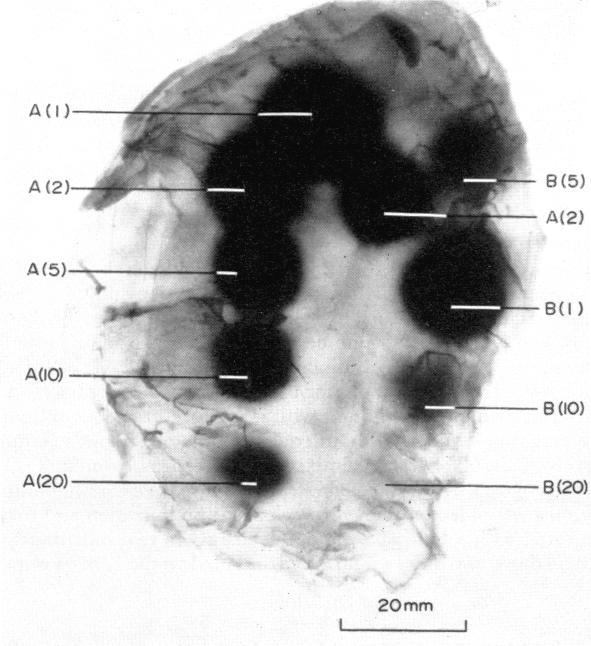

Rats were injected intradermally with rabbit anti-ovalbumin serum and 3 hours later were challenged intravenously with ovalbumin and Evans Blue dye. Inflammatory lesions were produced within 20 minutes and their size was markedly dose-dependent. Attempts were made to interfere with this passive cutaneous anaphylaxis (PCA) by admixture of normal IgG with the rabbit anti-ovalbumin to measure the relative tissue binding affinities of IgG from various species. It was found that normal IgG from any of the species tested had an enhancing effect on PCA in rats. These immunoglobulins serially arranged in the order of their decreasing enhancing abilities were: bovine>guinea-pig>pig>rat>rabbit>horse>human. The extent and significance of the enhancement increased considerably with increasing concentration of IgG in the test doses. The mechanism of enhancement was investigated and a hypothesis was proposed to explain the phenomenon.

给大鼠皮内注射兔抗卵清蛋白血清,3小时后静脉注射卵清蛋白和伊文思蓝染料。20分钟内产生炎症损伤,其大小呈明显的剂量依赖性。通过将正常IgG与兔抗卵清蛋白混合来干扰这种被动皮肤过敏反应(PCA),以测量来自不同物种的IgG的相对组织结合亲和力。结果发现,所测试的任何物种的正常IgG对大鼠的PCA都有增强作用。这些免疫球蛋白按增强能力递减的顺序依次为:牛>豚鼠>猪>大鼠>兔>马>人。随着测试剂量中IgG浓度的增加,增强的程度和意义显著增加。对增强机制进行了研究,并提出了一个假说来解释这一现象。